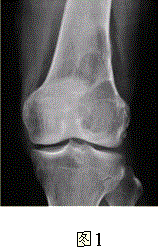

问题 患者女,35岁,左膝关节隐痛1年余,近1周加重,活动后明显疼痛。查体:左股骨下端外侧肿胀,压痛。行左膝关节正侧位CR,并行左膝关节CT扫描,见下图。 对本病例,应首先考虑的诊断是

选项 A.动脉瘤样骨囊肿 B.骨囊肿 C.成软骨细胞瘤 D.骨结核 E.骨巨细胞瘤 F.非骨化性纤维瘤

答案 E